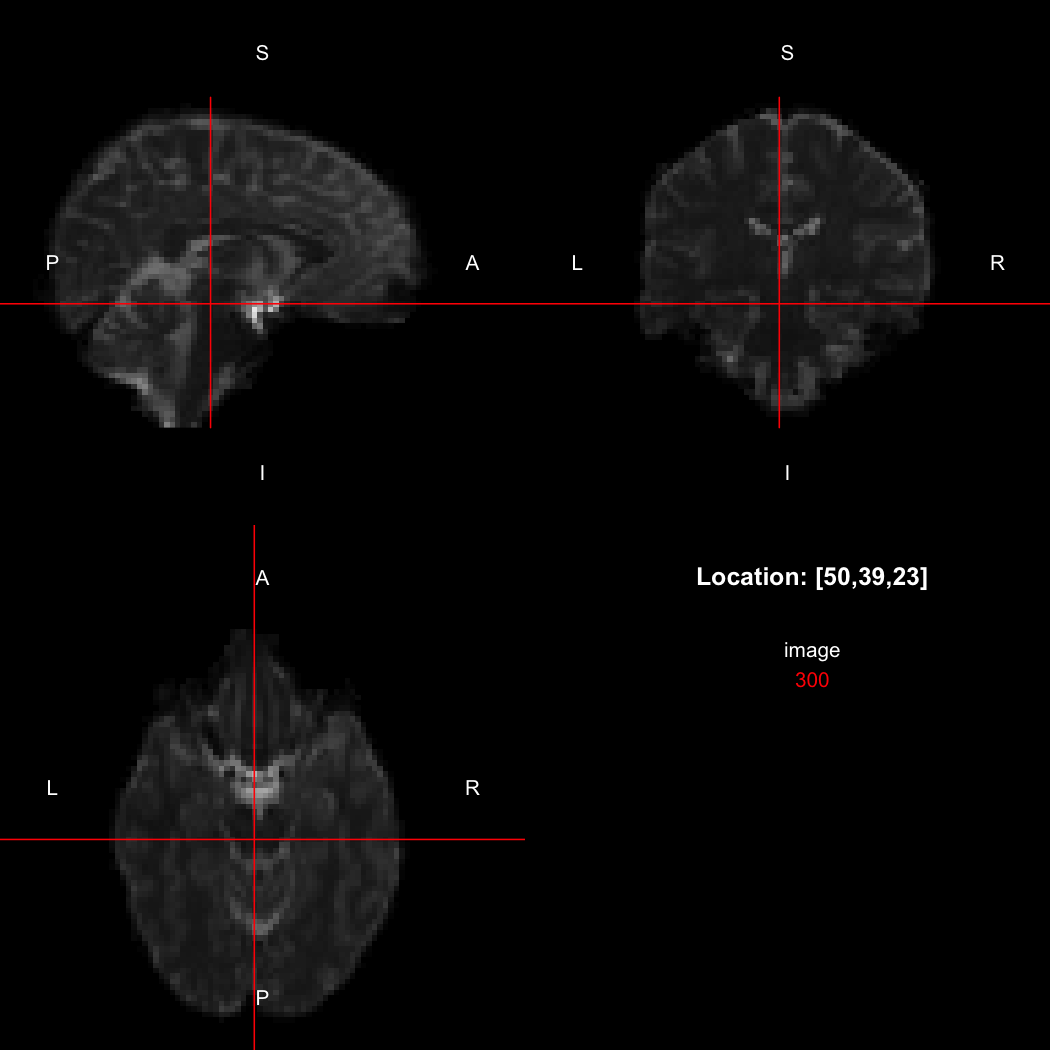

remotes::install_github("jonclayden/imbibe")The first step for any usage of the package is to create or read in

an image. We will use a 3D medical image from the RNifti

package by way of an example.

image <- readNifti(system.file("extdata", "example.nii.gz", package="RNifti"))We can also use the RNifti image viewer to visualise the

image.

view(image)